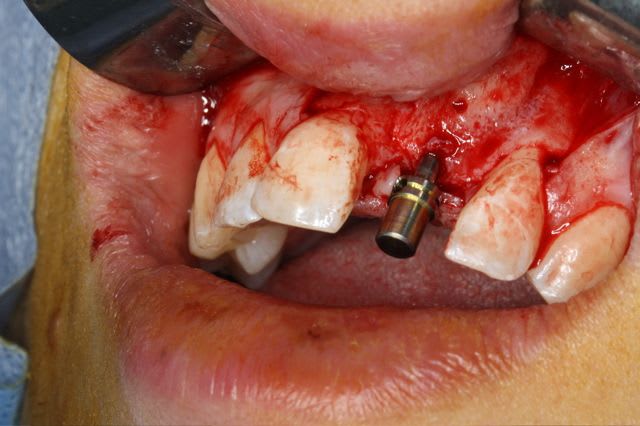

Pour le fun ! car pas bcp de photos en ce moment sur nonol

la dent était absente depuis 8 ans suite à "accident" de la vie (à 5h du mat'...)

très classiquement:

greffe onaly,

dépose des vis et pose de l'implant à 5mois1/2 avec un cj roulé et mise en place de la vis de cica,

et 3 mois 1/2 après empreinte

15j après essayage pilier et biscuit, visite au labo pour "finition en bouche" et 3 h après scellement.

pour la greffe: un lit de copeaux généreux et un bloc corticale par dessus et des copeaux pour boucher les espaces. Pas de membrane par dessus, seulement le périoste.